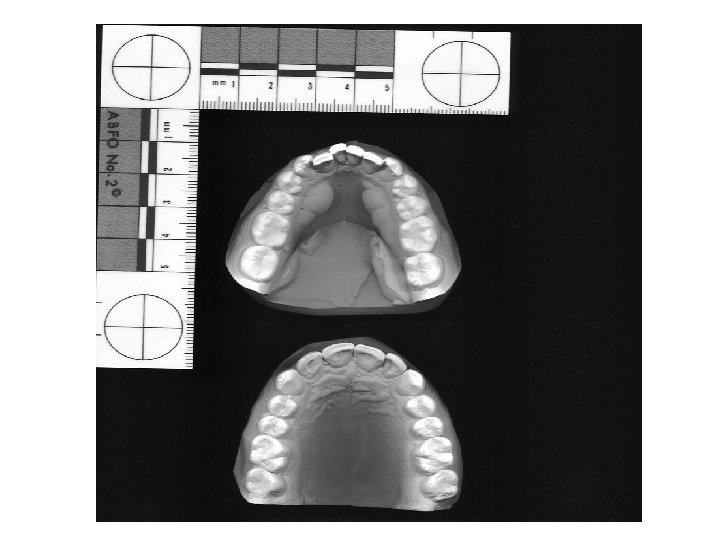

Teeth Impressions • Can be left in food, gum and skin

Teeth Impressions • Connect suspect to bite mark: